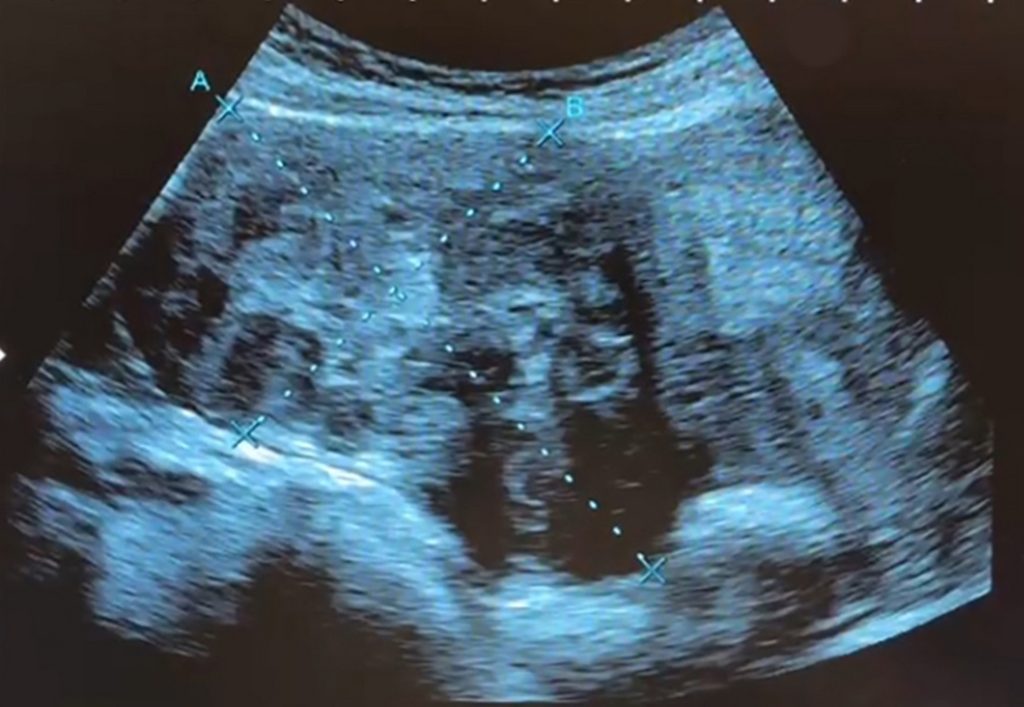

一位35歲上班族女子即將結婚,擔心多年來檢查發現的多顆子宮肌瘤會造成不孕,婚前就醫檢查,發現體內子宮肌瘤又多又大,是屬於年輕型的子宮肌瘤患者,因體質及年紀輕,血中雌激素刺激讓子宮肌瘤快速長大,患者接受達文西機械手臂手術,由肚臍開刀取出9顆肌瘤,從1到9公分不等共9顆,最大肌瘤大如拳頭般,但手術沒有明顯傷口,把傷口隱藏在肚臍裡。

謝昌興表示,患者的子宮肌瘤不是長在子宮腔內,而是長在子宮璧並往外生長,子宮猶如圓凸形,這類子宮肌瘤在手術摘除後,子宮的功能恢復正常,能自然受孕及生產;如果肌瘤往子宮腔面生長,可能有不孕問題。